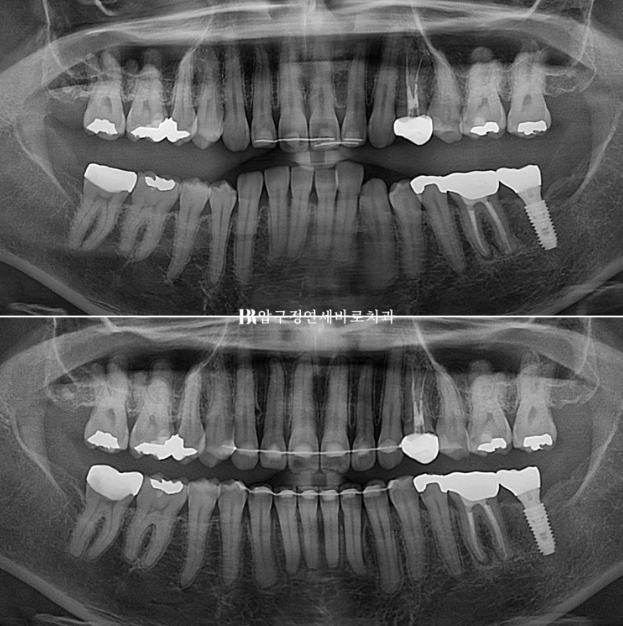

24.01~24.12

파노라마상 초진때 솟아올라와 있던 아래 앞니가 상당량 함입된 것이 보입니다.